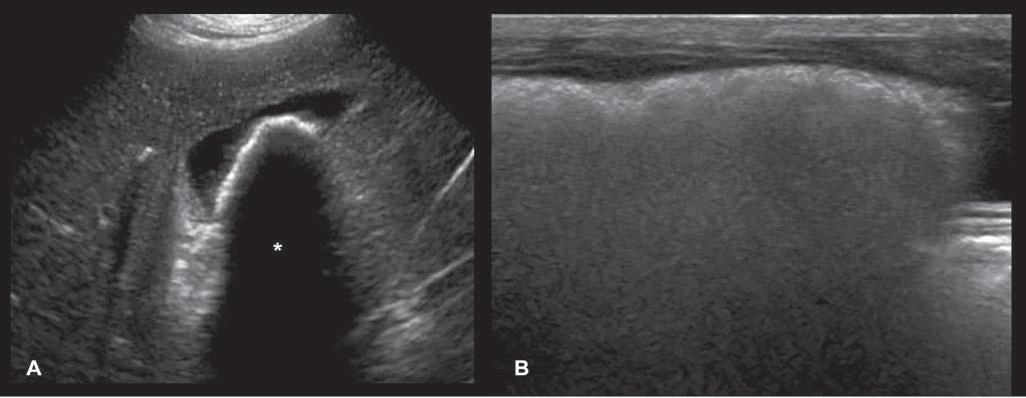

Edgeshadowing appearsasdiscrete,triangular zonesoflowamplitude,attheedgeofacurved structure(Figure1.14A).When,thecurvedstructure isfluidfilled,theedgeshadowingartifactbordersthe enhancementartifact.Thistypeofrefractiveshadowingcanbeconfusing,especiallywhenitoccursatthe

cranialaspectofafluidfilledbladder,andappearsas a“defect”ofthewall(Figure1.14B).

Figure1.14. Edgeshadowingandrefraction.A,B: Edgeshadowing(arrowheads)isoftenseeninprolongationoftherenal pole.LK,leftkidney. C: Thecurvatureofthebladderwallcausesbeamrefraction,whichresultsinanacousticshadow(arrowheads)inthisdogwithechogenicperitonealeffusion(*).Aholeinthebladderwall(arrow)isartifactuallycreated. D: Inanother dogwithcardiactamponadeandmarkedperitonealeffusion(*),theartifactualholeinthebladderwall(arrow)isattenuated byrepositioningthetransducerwithadifferentangulation.